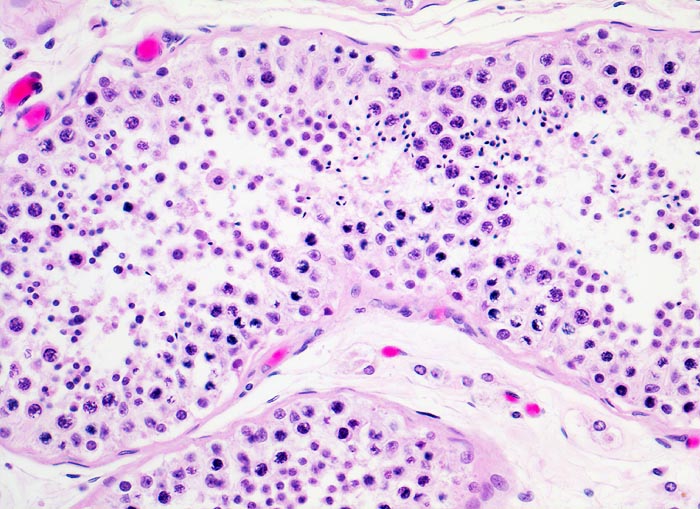

Basel 3BA HS/ Embryonales Karzinom des Hodens

Embryonales Karzinom des Hodens

Histologisch bilden die Tumorzellen solide Zellplatten, Drüsen oder papilläre Strukturen mit Einblutungen und Nekrosen. Die Tumorzellen sind polygonal, kubisch oder zylindrisch, haben reichlich Zytoplasma und unscharfe Zellgrenzen. Die grossen Kerne haben grob verklumptes Chromatin und enthalten oft mehrere sehr grosse unregelmässige Nukleolen. Gefässeinbrüche und eine testikuläre intratubuläre Neoplasie sind in der Tumorumgebung häufig nachweisbar

Morphologische Merkmale:

• Kein residuelles nicht neoplastisches Hodengewebe.

• Polymorphe Tumorzellen bilden miteinander anastomosierende Stränge, solide Zellplatten, glanduläre und kribriforme Strukturen.

• Sehr grosse, pleomorphe und hyperchromatische Zellkerne mit prominenten Nukleolen.

• Tumornekrosen.

• Mitosen und Apoptosen.

• Reichlich ödematöses Stroma mit einzelnen synzytiotrophoblastären Riesenzellen.

• Gefässeinbrüche in peritumoralen Gefässen.

• Tumorinfiltration des peritestikulären Fettgewebes.